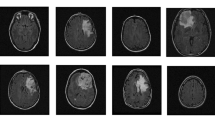

Glioma is a prevalent and deadly form of brain tumor. Most of the existing models have used 2D MRI slices for general tumor classification. In this paper, a 3D convolutional neural network has been proposed to automatically classify gliomas namely, astrocytoma, oligodendroglioma, and glioblastoma from MRI images. MRI modalities like T1, T1ce, FLAIR, and T2 are used for glioma classification. This step is essential for diagnosis and treatment planning for a patient. Manual classification is costly, time-consuming, and human-error prone. So, there is a need for accurate, robust, and automatic classification of glioma. Convolution neural networks have achieved state-of-the-art accuracy in many image processing classification tasks. In this work, 3D and 2D CNN models have been studied with multiple (T1, T1ce, FLAIR, and T2) and single (T1ce) MRI image modalities as input. The effect of segmentation of glioma on the classification accuracy has also been studied. The CNN models have been validated on the publicly available CPM-RadPath2019 dataset. It has been observed that the 3D CNN with segmented glioma along with multiple MRI modalities (T1, T1ce, FLAIR, and T2) has achieved an overall accuracy of 75.45%.